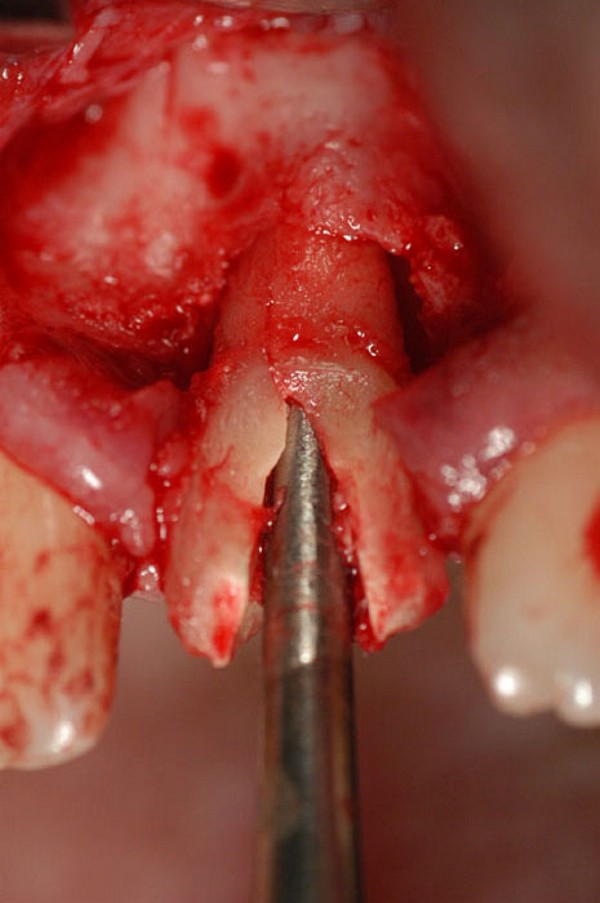

Abstract: Las fuerzas anterógradas traumáticas son en general las causantes de fracturas radiculares en el sector anterior de la boca. Desarrollo: El paciente se presenta a la consulta , con la fractura de una funda de porcelana inyectada en la zona cérvico palatina, solicitando simplemente la reparación en boca para evitar rozamientos linguales. Dicha funda con un perno colado en oro y su correspondiente endodoncia, habían sido realizadas en mi clínica varios años atrás, con un «aparente éxito total». Radiograficamente, se encuentra una fractura radicular cercana al tercio gingival Observada la oclusión de las piezas anteriores, podemos ver que el vínculo ideal de Acoplamiento, no se cumple, habiendo una relación de franco contacto la que ha provocado la fractura. Llevando al paciente a Oclusión en Relación Céntrica, podemos ver el espacio a nivel anterior, correspondiente a la centricidad mandibular. En esa misma posición , es dable percibir una faceta parafuncional mesial del primer premolar superior… …que antagoniza con una faceta parafuncional distal del canino inferior… ..constituyendo un plano inclinado que provoca la antelación mandibular o Discrepancia Horizontal, fracturando la raiz del incisivo central. Extraida la porción coronal de la raiz, pensamos en la realización de un Implante Inmediato, a pesar de la presencia de una fístula dado que se trataba de un central, decisión que obtuvo éxito implantario mas no estético, según veremos luego. Era fundamental conservar lo mas posible las tablas óseas, que de hecho había perdido la porción cervical Realizamos una incisión que conservara las papilas de las piezas adyacentes. Realizamos la exodoncia mediante un instrumento construido «ad hoc» que denomino: Con lo que obtenemos la preservación «ad integrum» de las corticales peridentarias remanentes. Instalamos entonces un implante T.B.R. de 15 mm de largo por 4 mm de diam. con cuello de zirconio de 3,5 mm …quedando tres espiras sin hueso por vestibular, producto de la tabla perdida, Incidimos el periostio a nivel apical del colgajo para obtener mayor paño quirúrgico, y legramos un bolsillo palatino sin incisiones de descarga, para la inserción de la membrana. Suplementamos la carencia ósea vestibular con «BIOSS» …e instalamos una membrana reabsorbible «BIOGUIDE» , que fijamos con el mismo implante, y calzamos por palatino. Suturamos Instalamos nuestra provisional previamente confeccionada, sobre un abuttment de titanio. Y controlamos radiograficamente Pasadas tres semanas del retiro de los puntos, observamos una cicatrización alta que nos muestra el anillo de zirconio del implante. ……………………………………………….. Transcurridos tres meses preparamos una nueva cirugía, dirigida a instalar un injerto autólogo de conectivo en el área del anillo, con un nuevo desplazamiento del colgajo vestibular. Tomamos tejido conectivo del paladar a nivel de los premolares, mediante una incisión mucosa «en libro», y disección del conectivo subyacente. Lo posicionamos en vestibular del anillo de zirconio y lo fijamos mediante sutura Y semanas después nos encontramos con un nuevo fracaso de orden estético. ……………………………………………….. En la actualidad, el caso esta estable , aún con su funda provisional, a la espera de un nuevo intento plástico, mediante Injerto Libre de Encia. ………………………………………………….. ESQUEMA MECÁNICO DEL FENÓMENO …que además de los hechos mostrados en el caso presentado, frecuentemente provocan en el sentido antero posterior los fenómenos de DISPERSIÓN ,en el maxilar superior…y de APIÑAMIENTO en el maxilar inferior. CONCLUSIONES: Además del rigor académico que nos convoca… esta; nuestra casa…nos otorga la confianza que solo da el saber que estamos siempre entre amigos, que cada vez son más. Por tanto es que debo decir: YO fui el responsable de dicha fractura… …porque… …..que hubiera sucedido si hubiera hecho todo el trabajo implantario sin ajustar previamente su oclusión? Seguramente a esta altura del caso…también hubiera fracasado el implante. Siempre decimos que se aprende de los errores más que de los aciertos, y Dr. Carlos A. Acuña Priano

Fig.17(Pie de foto: Preservación de la cresta remanente)

Fig.18(Pie de foto: Instalación de Implante)

Fig .19(Pie de foto: espiras al descubierto)